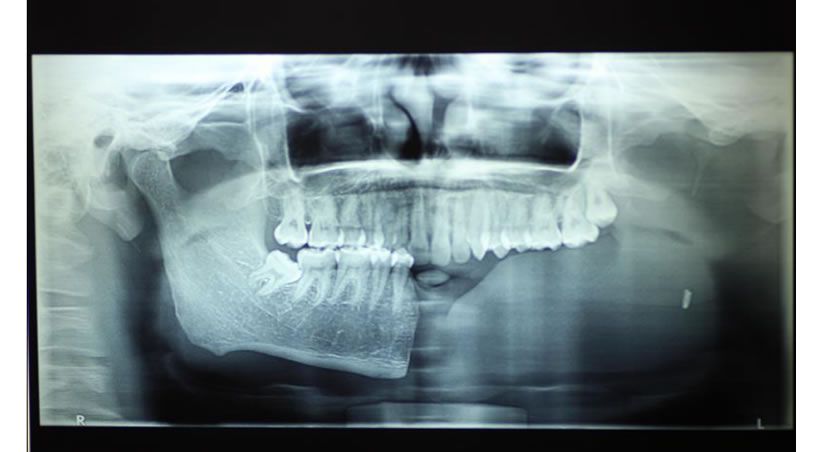

Manejo Protésico de un paciente con hemimandibulectomía

utilizando un plano protésico guía con rampa acrílica: informe de un caso